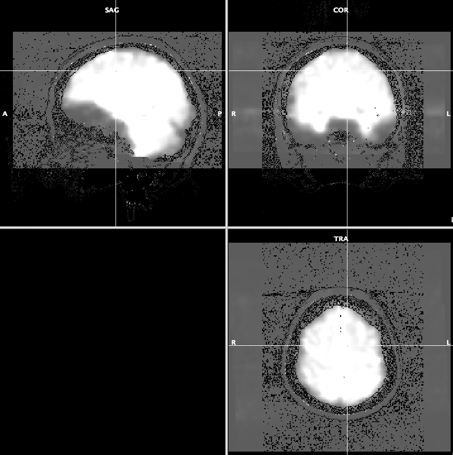

- Click "Iso-Voxel" and you will see "Iso-Voxel Transformation" dialogue. Check the Source voxel size is correct and press "OK".

-> You will get anat.low_SAG_ISO.vmr file.